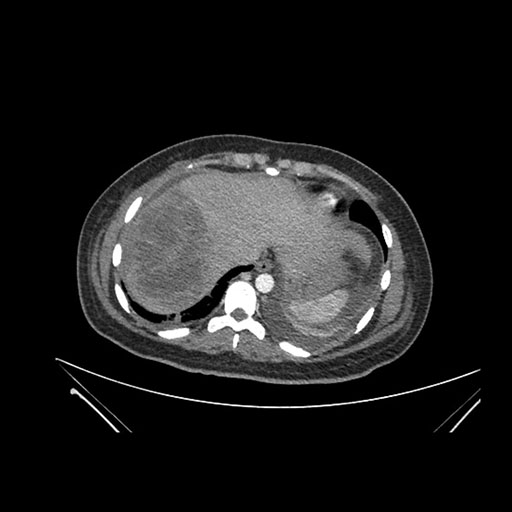

Axial Arterial

Axial Venous